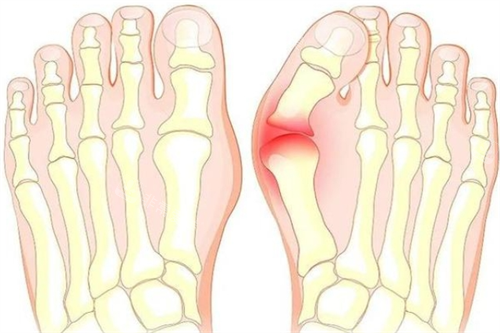

随着病情的发展,大脚骨部位会逐渐出现红肿、疼痛加剧的情况,重的时甚至会影响到正常的行走姿势,导致身体其他部位如膝关节、腰椎等出现额外的压力,引发连锁反应的健康问题。

中度大脚骨患者的拇趾外翻程度加重,疼痛症状更加明显,可能已经出现了局部的红肿、鸡眼等问题。

重度大脚骨患者的拇趾外翻角度较大,可能已经影响到了其他脚趾的正常排列,导致脚部功能重的受损。